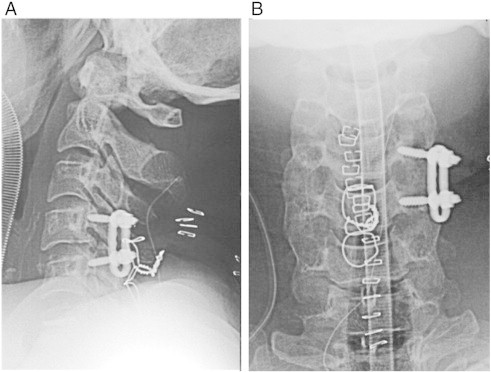

Fig 3.

A and B, Plain radiographs taken after surgery shows solid fixation of C4-5.